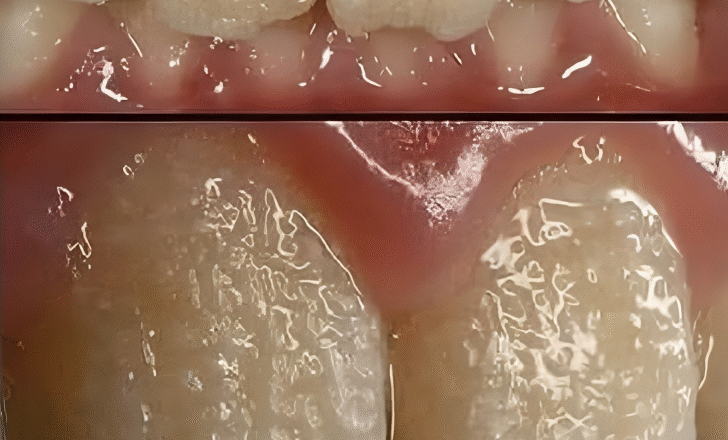

Ласкаво просимо до світу недосконалого амелогенезу (НА) — рідкісного генетичного захворювання емалі, яке може зробити ваші зуби головною темою для розмов (на краще чи на гірше).

Штучний інтелект — це не типова стоматологічна проблема. Це ніби ваша емаль страйкувала, залишивши зуби з дефектним захисним екраном. Чи то відсутність емалі, погана якість, чи просто порушена структура, це ніби ваші зуби мають нестандартний вигляд, але не найкращий вид нестандартного виробу.

Штучний інтелект не має стандартної збірки. Він може змінюватися від легкої, але незначної зміни кольору до сцени повної драми з серйозною втратою емалі та зубами, які можна сплутати зі стародавніми реліквіями. А що насправді? З часом все може погіршитися, якщо це не контролювати.